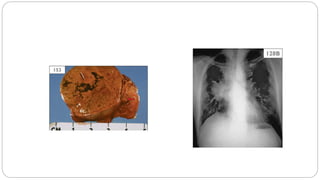

• #26 Adrenal cortical adenoma associated with Cushing syndrome: a well encapsulated 3.6 cm yellow-tan intra-adrenal mass with focal hemorrhage. Normal adrenal tissue is seen to the right (arrow).